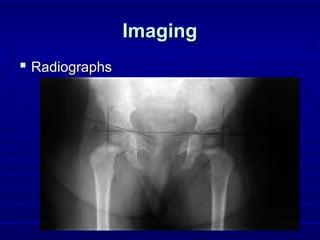

ImagingImaging

 RadiographsRadiographs